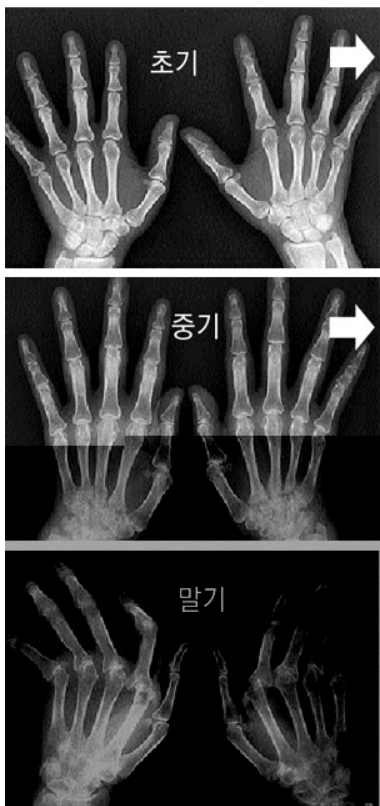

✅ 2 .류마티스 관절염이란?

류마티스 관절염은 자가면역질환입니다.

우리 몸의 면역체계가 잘못 작동해, 정상 관절을 공격하면서 염증과 통증을 유발하는 병이에요.

1.주요 증상 체크 리스트

- 양쪽 손가락·손목·발목 마디가 동시에 붓고 아픔

- 아침에 손이 굳은 듯 뻣뻣한 느낌 (30분 이상 지속)

- 관절을 움직이면 열감과 통증이 심해짐

- 피로, 미열, 식욕 저하 등 전신 증상도 동반

아침에 손가락이 잘 안 펴지고, 컵을 잡는 것도 힘들다면,

특히 ‘대칭적으로’ 아픈 게 일반 관절염과 다릅니다.